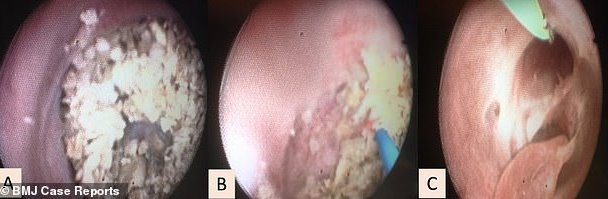

El conducto urinario, antes (Izq.) y después (Der.)

A la mujer, de 22 años, que recibió el falso pene en 2014, además de los pelos, se le formaron docenas de piedras pequeñas, similares a los cálculos renales en el conducto urinario. Exactamente no se puede decir uretra, porque la uretra es un canal que la gente tiene con el nacimiento, pero este es un canal de un pene falso. En todo caso, es el conducto que hace las veces de uretra.

Finalmente, para tratar las piedras, que impedían a la mujer orinar correctamente, resolvieron disolverlas con un láser, en una especie de litotrisia uretral.

Con el tiempo, desde su implantación en 2014, el conducto urinario de esta mujer se había estrechado y tenía pelos pequeños en su interior que podrían haber acelerado el desarrollo de las piedras. Además, en el órgano artificial, el suministro de sangre no es lo suficientemente bueno y el canal urinario puede ser inusualmente ancho o estrecho.